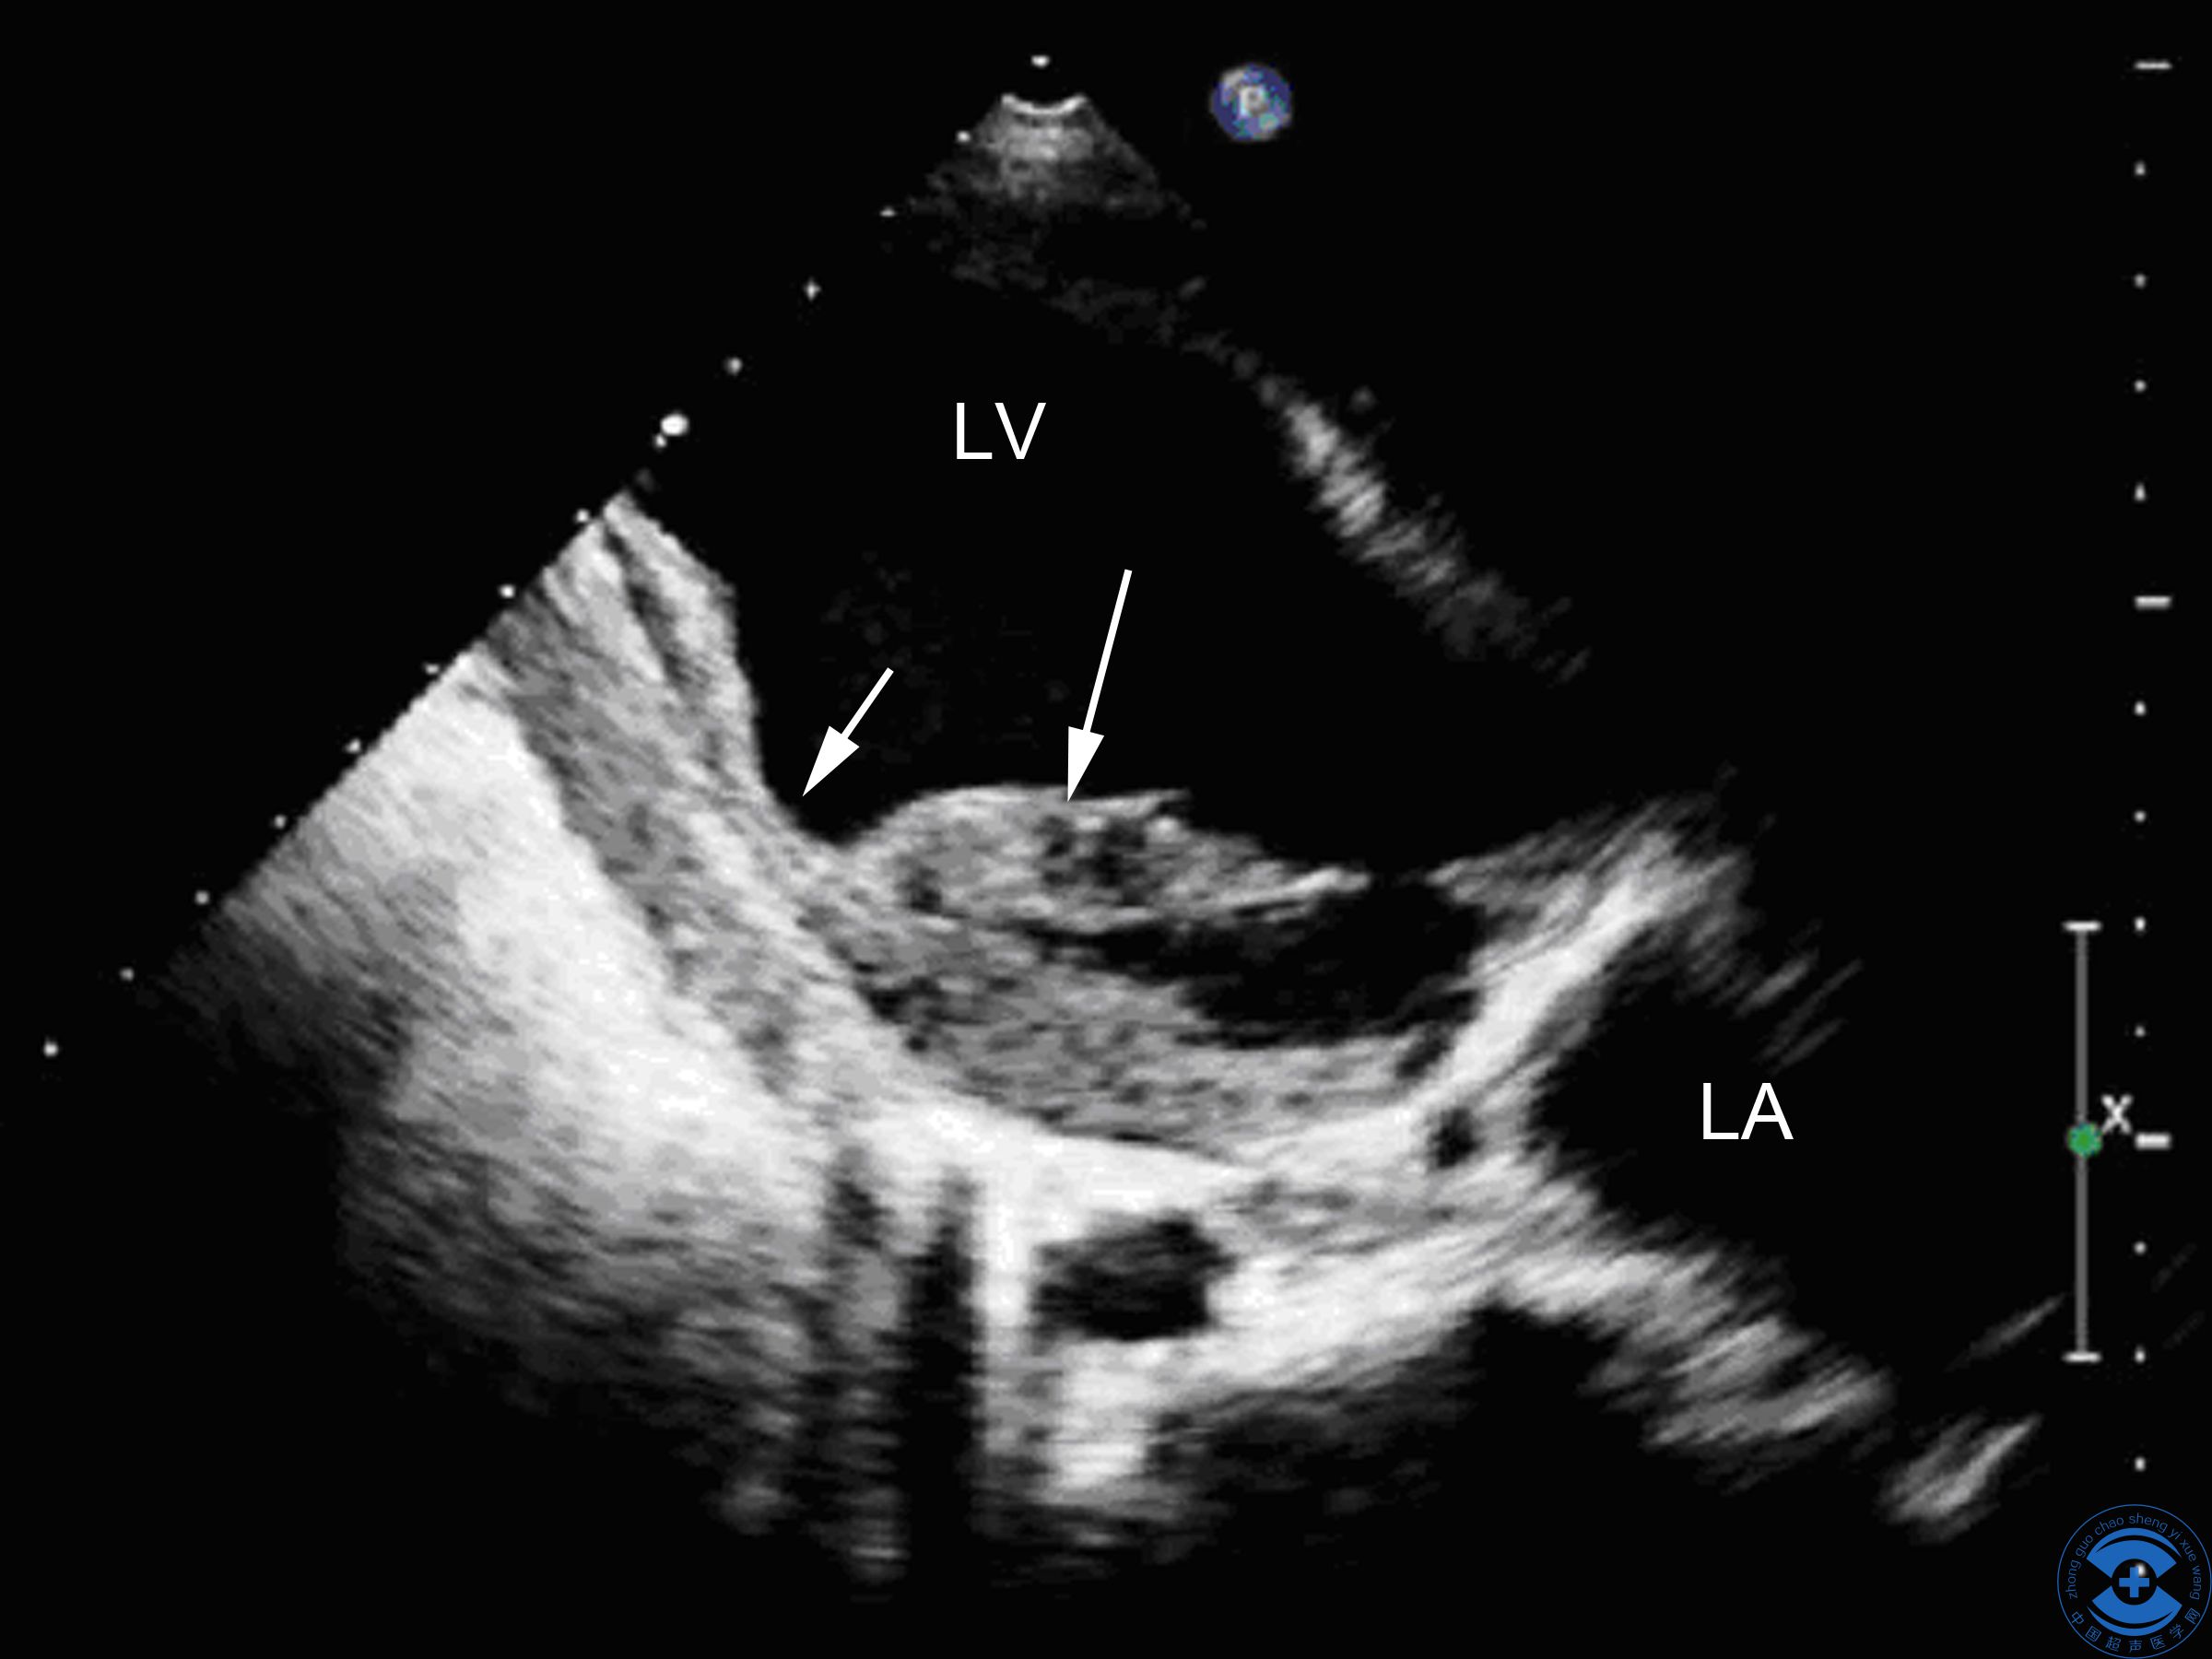

图3室间隔内裂隙:探头由心尖两腔心切面向下倾斜,箭头所示为带状非贯通性撕裂伤

室间隔穿孔及左室后壁不完全性撕裂伴二尖瓣脱垂